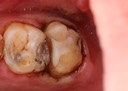

Joe Cha #18 amalgam removal

Joe Cha #18 prep